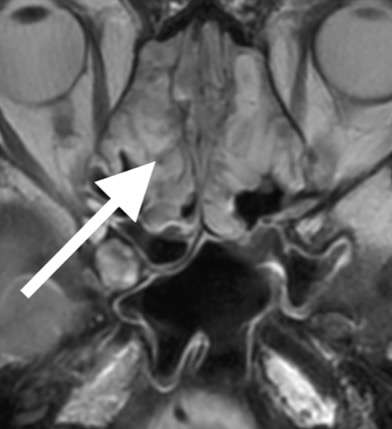

33歳女性、元々左上の奥歯に虫歯があり、歯科で治療後も改善しないため受診。頭部MRI検査で左上顎洞に炎症を認めました。したがって、奥歯の感染がすぐ上の上顎洞へ波及した「歯性上顎洞炎」と考えられました。